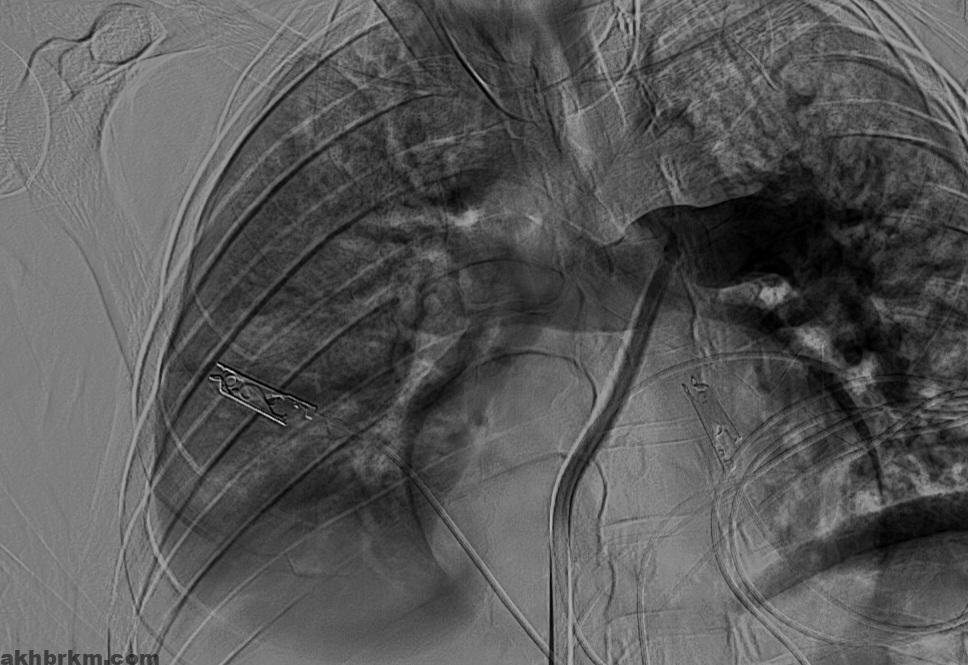

وكان المريض قد نُقل بشكل إسعافي من أحد المستشفيات وهو في حالة حرجة ، نتيجة معاناته من ضيق شديد في التنفس وانخفاض حاد في مستوى الأكسجين ، إثر انسداد كامل في الشريان الرئوي الرئيسي بسبب خثرات وريدية عميقة ظهرت بعد خضوعه لعملية منظار لمفصل الركبة.

وبفضل سرعة الاستجابة وجاهزية فريق الأشعة التداخلية جرى التدخل العلاجي العاجل وفتح الشريان الرئوي وسحب الجلطة بالكامل بدقة عالية ، ما أدى إلى تحسّن فوري في العلامات الحيوية واستقرار الحالة دون تسجيل أي مضاعفات.